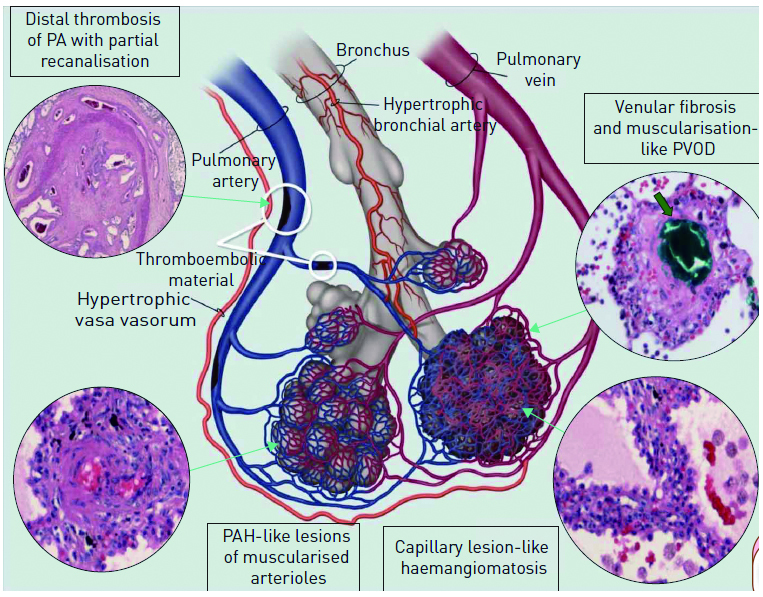

无血栓阻塞的肺动脉在CTEPH发展中扮演什么样的角色呢?很有意思的是,研究发现未被阻塞的肺动脉会出现同样的病理变化。原因是肺动脉阻塞后,支气管动脉及肺后动脉之间的连接部位因压差升高而扩张以改善肺灌注,但同时将未被阻塞的小动脉暴露在高压力下而导致内皮功能障碍(图 1),出现与特发性肺动脉高压相似的血管损伤如内膜增厚,阻力血管重建,内膜纤维化,内膜肌纤维增生及致丛样病变等,甚至影响远端肺动脉,导致肺血管阻力增加逐渐发展为症状性CTEPH[31-32]。除此之外,NO-sGC-cGMP信号传导通路与远端肺动脉损伤密切相关,CTEPH患者内皮细胞的一氧化氮合酶激活物不对称二甲基精氨酸的水平升高,而NO的水平降低,NO通路等抗增殖机制紊乱可能对CTEPH患者血管的重建产生重要影响[33]。不宜行PEA及术后复发的CTEPH患者经sGC激动剂(利奥西呱)治疗后临床症状及血流动力学明显改善,可从侧面佐证NO-sGC-cGMP信号传导通路在CTEPH发展中的重要作用[34]。